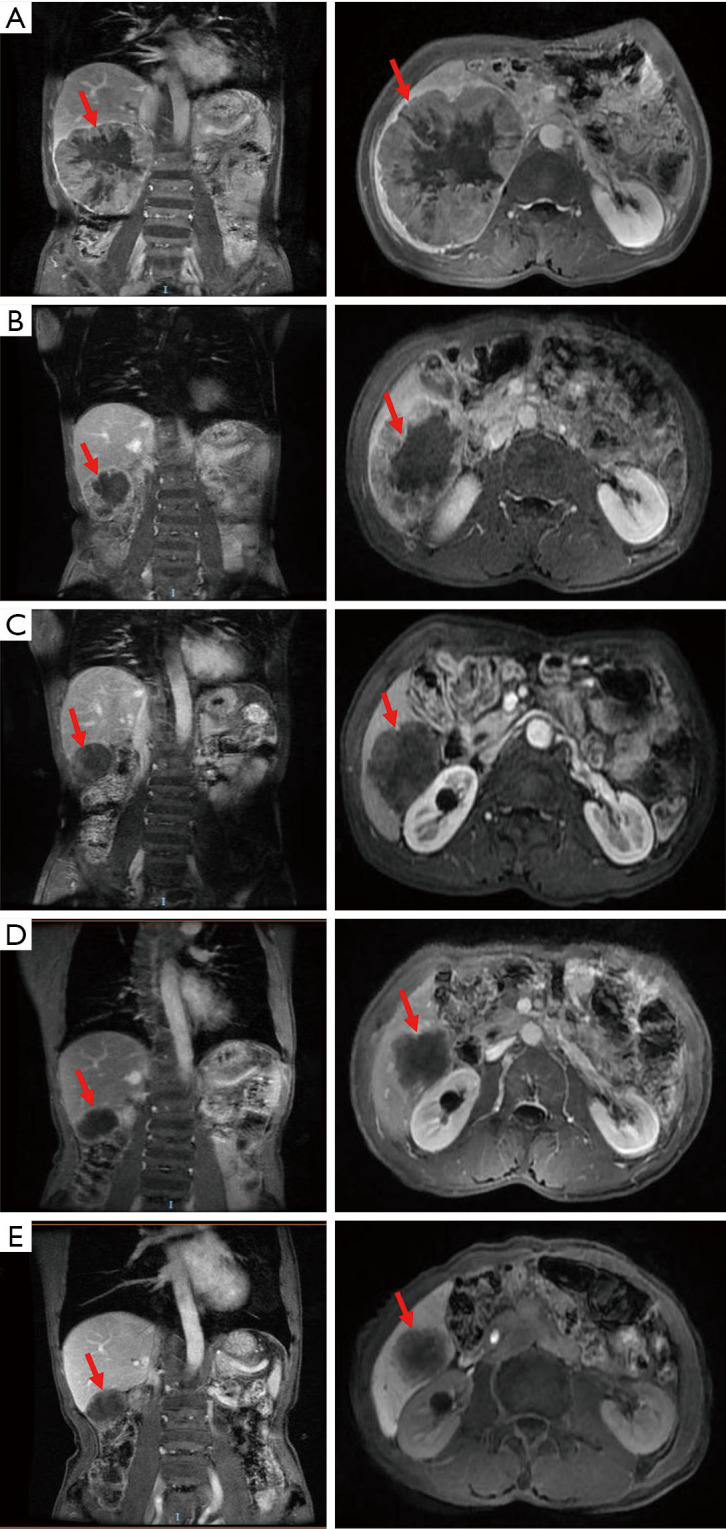

Case description: We present a patient with Barcelona Clinical Liver Cancer Stage C huge HCC who was treated with combined targeted therapy and immunotherapy as the primary therapeutic regimen, supplemented with tegafur long-term metronomic chemotherapy, as well as specialized adjuvant therapy such as thymosin, bisphosphonates, antiviral medication, and vitamin C supplementation. The tumor size was significantly reduced and microwave ablation was performed, after which, the patient was kept on the combination regimen, resulting in a partial response (PR), and maintaining PR without disease progression for 32 months.